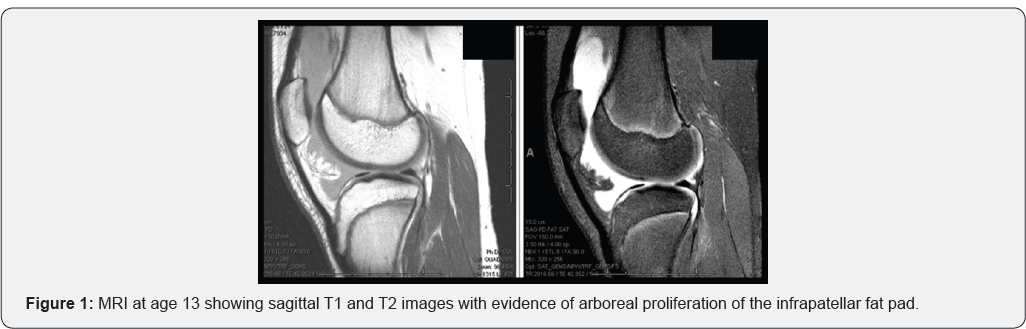

The patient was a 19-year-old male referred to our clinic following six years of recurrent knee effusions and two recent episodes of left patella dislocation events. He had congenital transposition of the great arteries, requiring an arterial switch procedure in infancy and a subsequent aortic valve replacement at age 9, resulting in long-term use of warfarin for anticoagulation. Pediatric orthopaedic and rheumatology specialists had attributed his effusions to be due to hypertrophic synovium from chronic hemarthroses when they began occurring in his early teen years. An MRI of his left knee at age 13 showed arboreal hypertrophy of the infrapatellar fat pad, though at the time this was not diagnosed as lipoma arborescens (Figure 1)